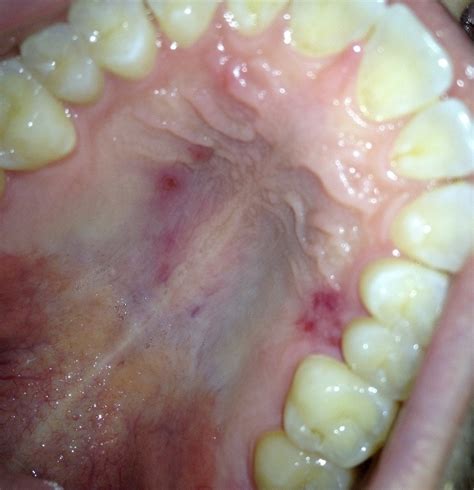

• redness on roof of mouth

• red sore spot in mouth

• rash on roof of mouth

• red spots on palate

• red sores roof of mouth

• red spots top of mouth